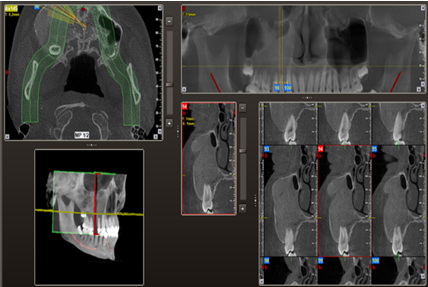

Estudios de imagen

Como estudio imagenológico inicial, se le realizó ortopantomografía, donde se apreció la lesión radiopaca de bordes irregulares y difusos en el cuadrante superior derecho que se extendió en sentido cefálico caudal con ocupación del seno maxilar derecho, y en sentido mesio-distal desde la unidad 1.3 hasta la unidad 1.7. Posteriormente se le indicó una tomografía computarizada cone beam, donde se apreció que el límite superior de la lesión coincide con el borde inferior del cuerpo malar, extendiéndose hasta el pilar cigomático maxilar, tal como se muestra en las Figuras 3, 4 y 5.

Figura 3. Reconstrucción 3D en una vista trans axial de los huesos del macizo cráneo facial y la zona afectada por la lesión. Fuente: Historia Clínica Postgrado Cirugía bucal ULAC-IDOLA Julio 2021

Figura 4. Reconstrucción 3D volumen rendering, en una vista frontal de los huesos de la cara y zona afectada por la lesión. Fuente: Historia Clínica Postgrado Cirugía bucal ULAC-IDOLA Julio 2021

Figura 5. Reconstrucción multiplanar donde se observa la displasia en cortes: axial, sagital y coronal. Fuente: Historia Clínica Postgrado Cirugía bucal ULAC-IDOLA Julio 2021